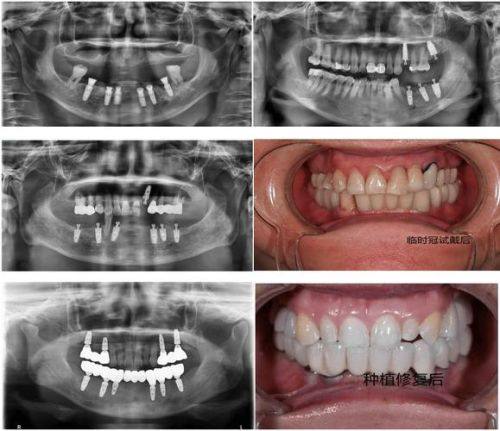

牙列缺失重建:可联合省级医师开展诊疗,根据患者牙列缺失情况制定专属重建方案,有效修复口腔咀嚼功能与面部美观度。

即刻种植、全口种植修复:联合省级医师开展诊疗,治疗过程重视细节,个性化制定种植方案,种植后牙齿稳固性好,修复速度快。